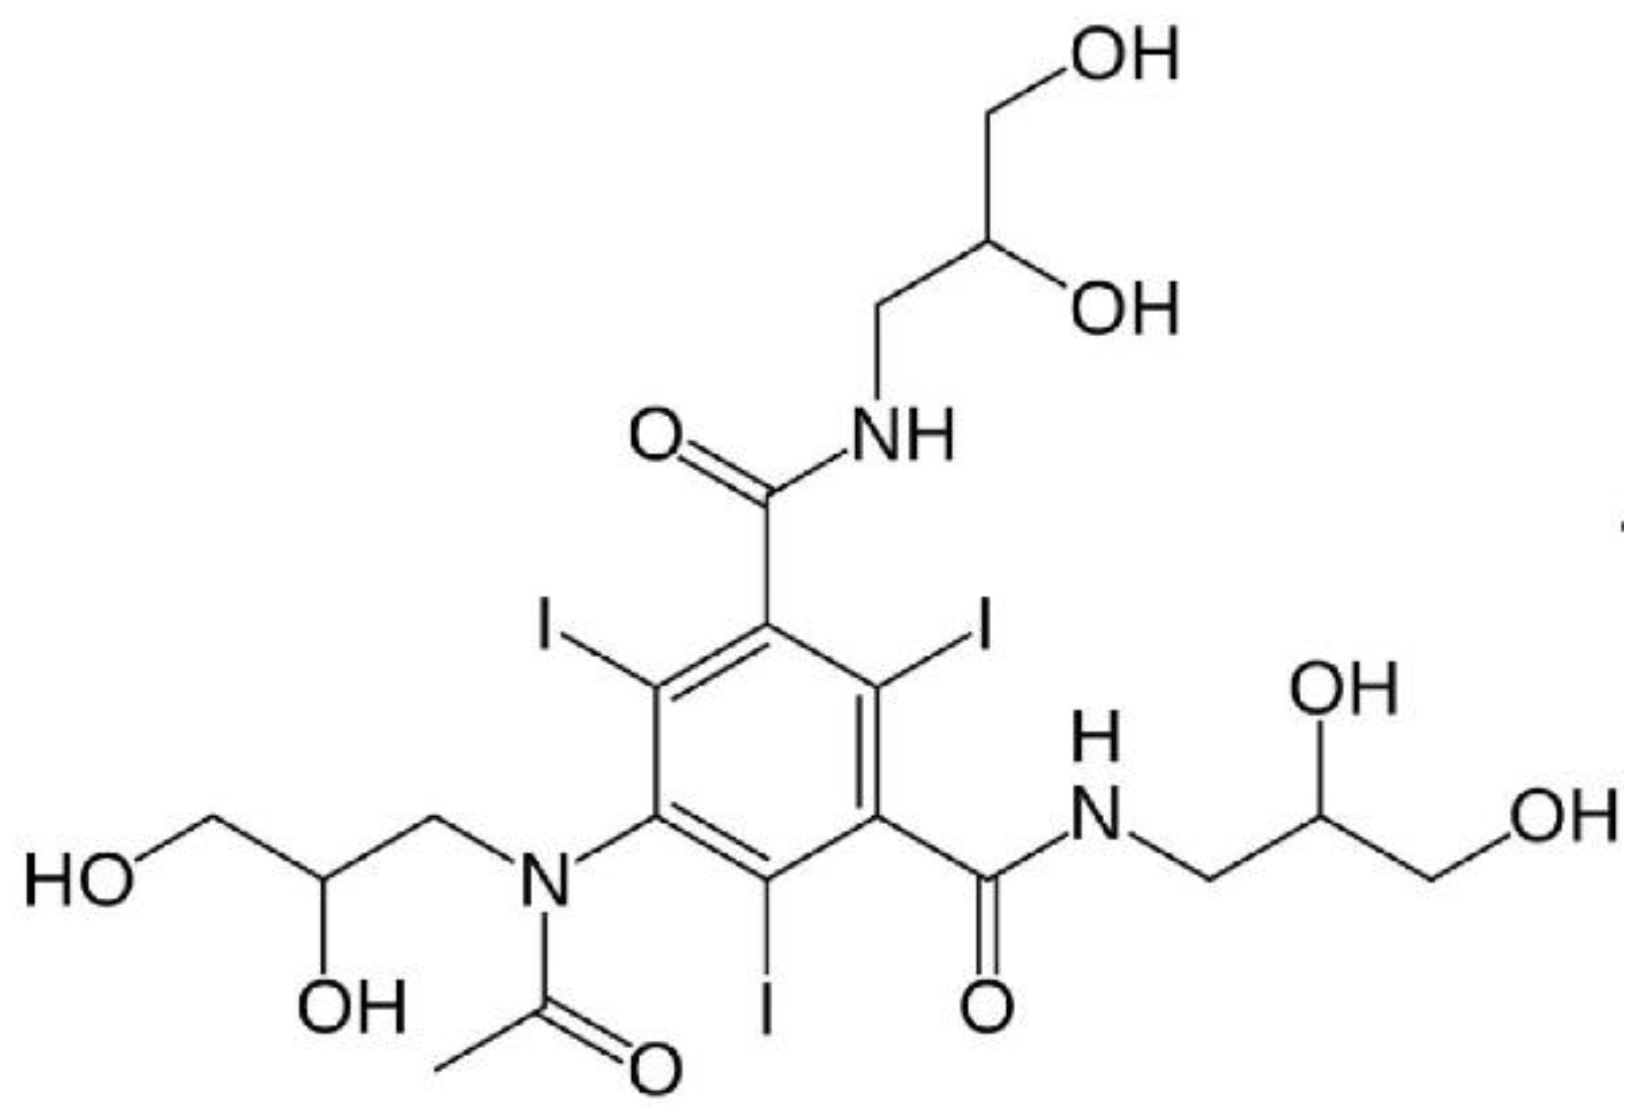

1.3. Iodine Nanoparticles

1.4. Iodine Nanoparticle Imaging